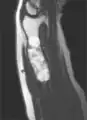

MRI showing enchondromas localized in the lower part of the radius of a 37-year-old patient affected with Ollier disease

MRI showing enchondromas localized in the lower part of the radius of a 37-year-old patient affected with Ollier disease.